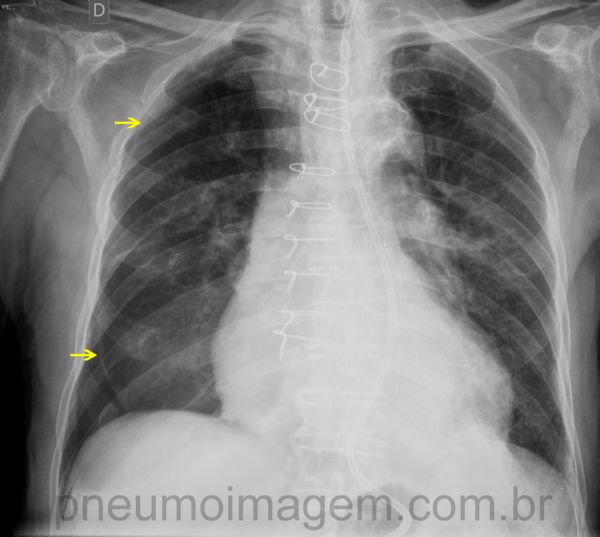

Pneumotórax à direita pós-punção pleural (toracocentese).

Observe a linha da pleura (setas amarelas) delimitando o pulmão colabado.

Velamento do seio costofrênico direito compatível com derrame pleural (hidropneumotórax).

Reexpansão espontânea parcial do pulmão após 3 dias de observação.

Ainda há pneumotórax residual na região inferior direita.